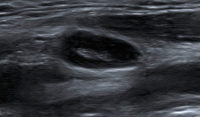

Abbildung 3: Lymphknotengröße. Bei diesem Lymphknoten aus dem Level 2 sind sowohl der Quer- als auch der Längsdurchmesser zu groß für diesen Halsabschnitt (quer max. 7–8 mm). „Diffuse large B-cell lymphoma“ (DLBCL).